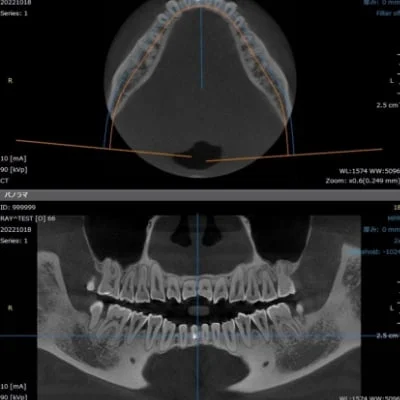

治療室・設備